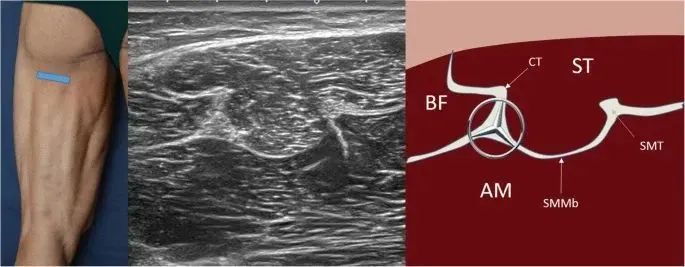

(圖5:大腿后部近中三分之一的短軸超聲視圖及對比圖。坐骨神經(jīng)的部分像奔馳標志。BF股二頭肌、ST半腱肌、AM大收肌、CT總腱、SMMb半膜肌腱、SMT半膜肌腱。)

圖中左側(cè)照片表示探頭定位該區(qū)域是指沿大腿近端,及三等分的中間交界處的短軸檢查。在這個水平上,坐骨神經(jīng)的部分可以很容易地識別為橢圓形或扁平結(jié)構(gòu),排列成束并被高回聲脂肪包圍。此結(jié)構(gòu)易于觀察,幾乎沒有各向異性。坐骨神經(jīng)位于明顯高回聲的三點星形中心,類似奔馳標志。

近端是(內(nèi)側(cè))半腱肌和(外側(cè))股二頭肌位于兩側(cè)的聯(lián)合肌腱。在這里,半腱肌 (ST) 部分比股二頭肌 (BF) 稍大。如果探頭移至近端,股二頭肌 (BF) 的尺寸會減小并呈現(xiàn)逐漸消失的三角形形狀。從該視圖來看,并且往近端方向上移動探頭,可見股二頭肌的游離肌腱。半腱肌 (ST) 部分一直可見到坐骨結(jié)節(jié)。從坐骨神經(jīng)的內(nèi)側(cè)部分出現(xiàn)一條與半膜肌膜相對應(yīng)的高回聲線,其終止于半膜肌腱(它是橢圓形的,比坐骨神經(jīng)小),幾乎與它平行。在這些肌肉的腹側(cè)是大收肌。